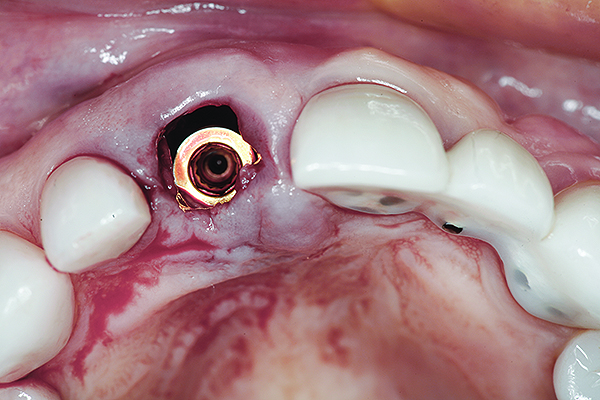

Without reflecting a full-thickness mucoperiosteal flap, the root tip was carefully extracted using periotomes to preserve the buccal plate and interproximal bone (Figure 3 and Figure 4). The extraction site was carefully debrided, and an osteotomy was prepared following the manufacturer’s instructions for placement of a 5/4mm D x 13mm L OSSEOTITE® Tapered Certain® PREVAIL® Implant (BIOMET 3i, www.biomet3i.com).

Fig 6. Implant insertion.

Figure 6

Fig 7. Occlusal view of the implant after insertion.

Figure 7